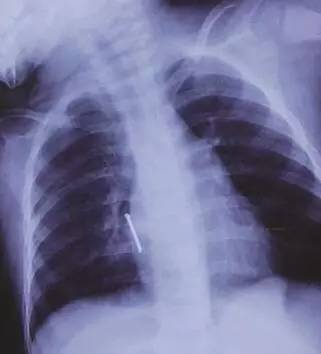

一瞬间,一把长5公分左右的钉子射进阳阳的心脏附近!据了解,气钉枪打出钉的力度很大,很有冲击力和*伤杀**力,速度一般60米/秒,厉害的可射穿1cm钢板!许先生看到此景,整个人都蒙了!带阳阳火速去医院,紧急抢救!

在进行充分评估后,专家们决定手术打开胸腔,后发现钉子的钉尖已经穿入右心房肌层3毫米,已造成胸腔积血150毫升!“如果钉子再深入一点,那抢救都来不及了。”所幸手术顺利,阳阳脱离了生命危险。